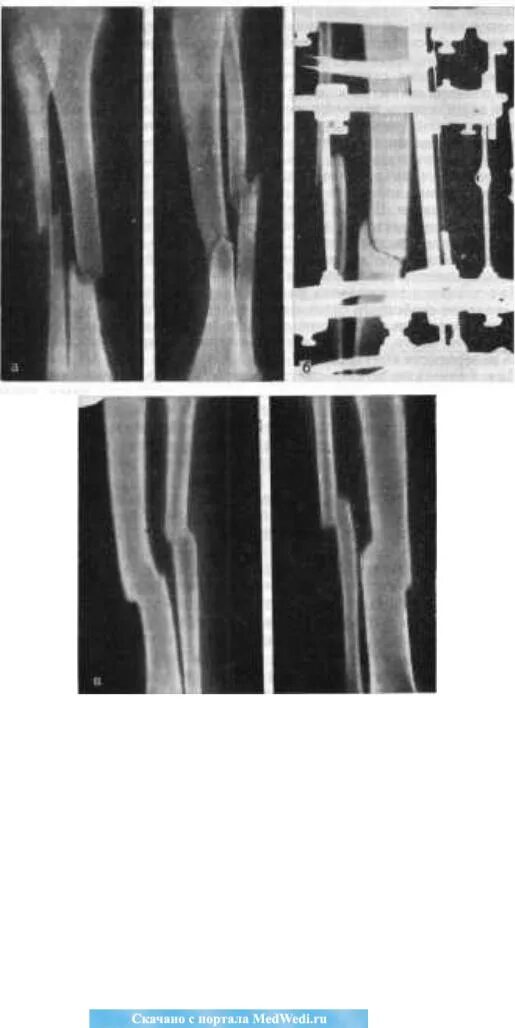

Оскольчатый перелом со смещением